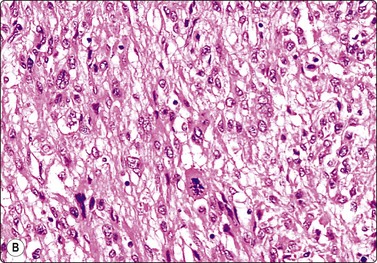

Sarcomas of the prostate are rare. These are mainly rhabdomyosarcomas in children, leiomyosarcomas (Fig. 13.21) or fibrosarcomas in adults (see Chapter 15).9,46

image

Fig. 13.21 Leiomyosarcoma of prostate

Tissue fragment of moderately pleomorphic spindle cells with eosinophilic cytoplasm; some loss of cell cohesion (H&E, HP).